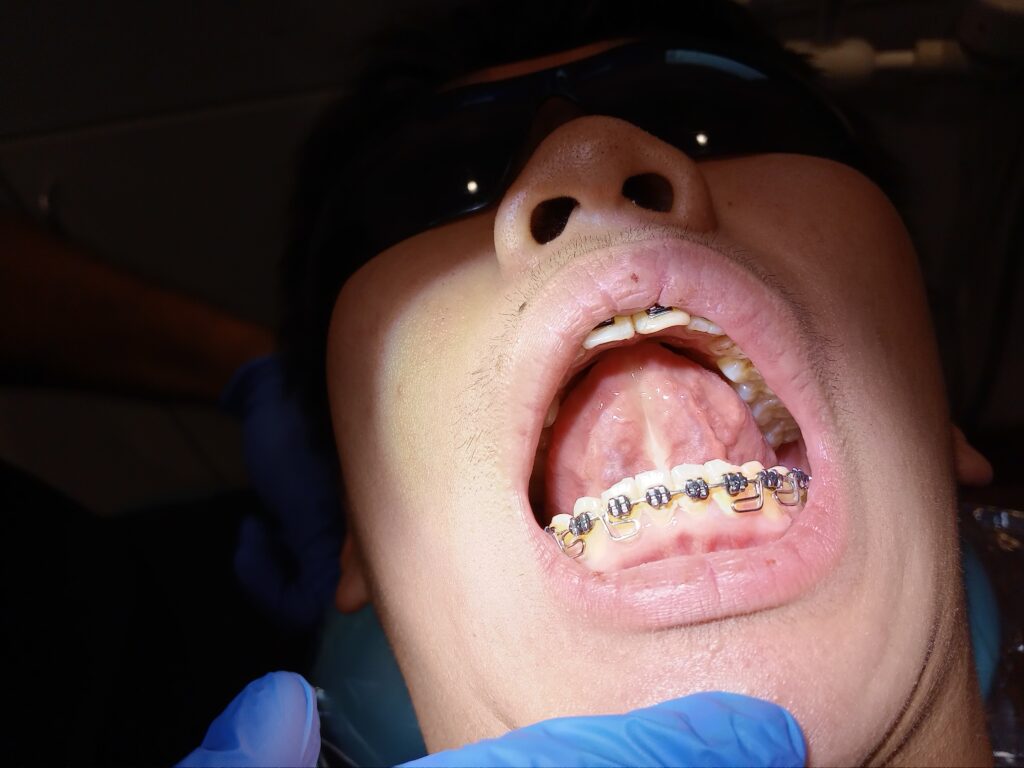

Frenuloplasty

View our results

Pre tongue surgery